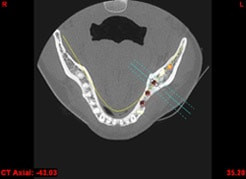

In komplexen Fällen, z. B. der Implantatversorgung eines kompletten Kiefers, oder bei schwierigen Knochensituationen bietet die 3-dimensionale Computerdiagnostik bzw. Planung und Durchführung erhebliche Vorteile und Sicherheit für den Patienten (siehe Bild 1 und 2).

Auf Basis einer computertomografischen (CT-) Kieferaufnahme ist eine dreidimensionale Darstellung der Knochen möglich. Der Zahnarzt kann dann am Computerbildschirm die Knochenqualität (z. B. Knochendichte) beurteilen und die optimale Position der Implantate im Vorfeld planen. Durch Verwendung spezieller Röntgenschablonen lässt sich auch die erwünschte Zahnstellung in die Planung einbeziehen. Die Simulation der OP erlaubt, das zu erwartende Ergebnis mit größtmöglicher Sicherheit vorherzusagen und dem Patienten am Bildschirm zu veranschaulichen.